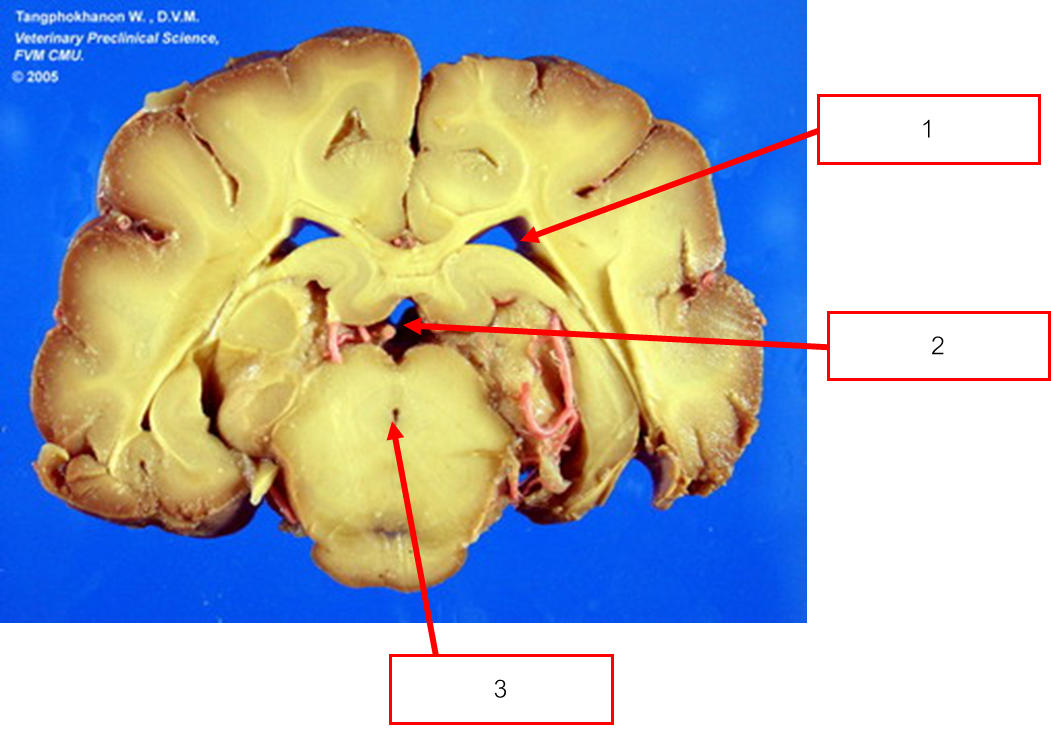

Histo ของ diencephalon

Corpus callosum

Interventricular foramen

Interthalamic adhesion

Third ventricle

Optic chiasm

Hypothalamus

Thalamus

Internal capsule

Lateral ventricle